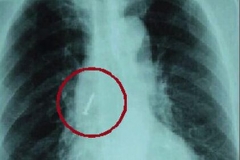

假牙遗落在肺里 导致老太持续咳嗽咳痰

人老后,牙齿不经用,不少人会选择佩戴假牙来帮助咀嚼食物。由于假牙需要睡前取下,不少老人记性不好,常常有弄丢假牙的事情发生。然而,若是不小心将假牙吞下,遗落在肺部...

2015-05-13查看详情